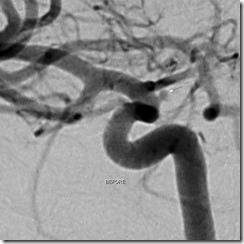

Fig 1: RICA injection showing the small aneurysm (arrow)

A cerebral DSA showed a tiny blister from the posteromedial wall of the right internal carotid artery. The aneurysm was so small and the location so unusual that coiling or surgery was not possible in this case.